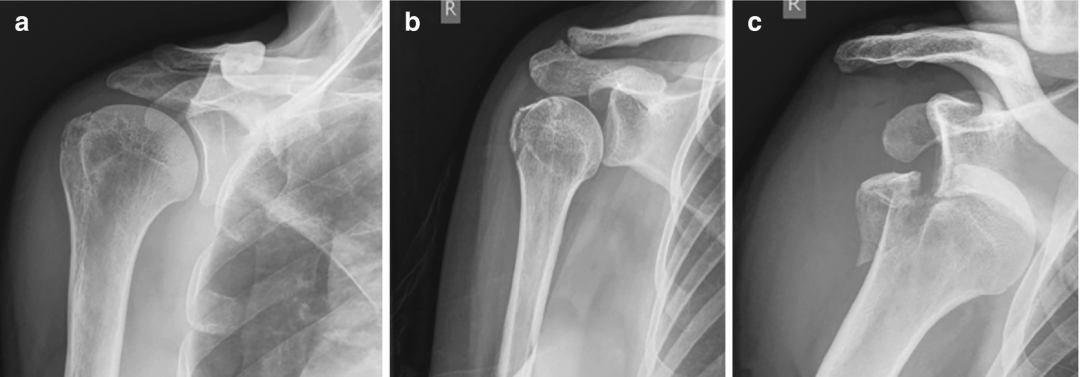

图1 AO/OTA Fracture and Dislocation Classification Compendium-2018

图2 肱骨近端大结节骨折AO分型示意图(a) 11-A1.1型无移位;(b) 11-A1.2型移位;(c) 11-A1.3型合并盂肱关节脱位